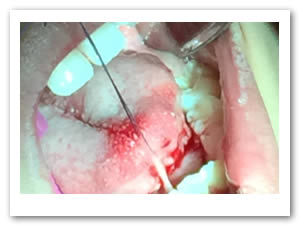

• Se eliminó el frenillo en su totalidad  con la ayuda de tijeras iris recta y hoja de bisturí del No. 15 así como todo el tejido residual fibroso correspondiente al frenillo. Se realizó genioplastia con pinza de mosco y disección roma para liberar adecuadamente la inserción frénica hasta la cara lingual de los incisivos inferiores. (Figuras  7, 8 y 9)

Figuras 7 y 8. Eliminación total del frenillo y genioplastia

Figura 9. Resultado obtenido después de genioplastia